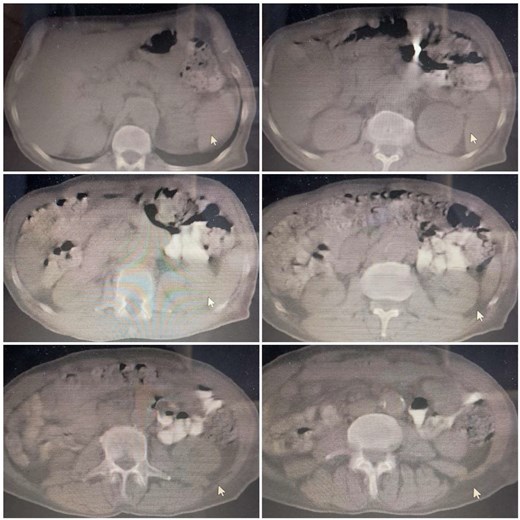

A 67-year-old male, with a smoking history of 40 pack-years, presented to the emergency department with an enterocutanous fistula. His medical history includes a prior laparotomy due to a gunshot wound, followed 6 months later by the development of an incisional hernia requiring surgical repair with the placement of a mesh patch. After 36 years of hernia repair operation, he developed an abscess, which was subsequently diagnosed and drained in another hospital. Three months post abscess drainage, the patient developed an enterocutanous fistula. On clinical examination, he exhibited grade II exertional dyspnea, orthopnea, and nocturnal paroxysmal dyspnea, with diminished breath sounds but no chest pain. Laboratory tests revealed normal urea and creatinine levels, mild anemia with a hemoglobin level of 10.8 g/dl, and elevated C-reactive protein at 150.4 mg/dl. Echocardiography and electrocardiography were both normal. A superficial abdominal ultrasound (US) detected a hyperechoic lesion with posterior acoustic shadowing extending 2 cm at the fistula opening, preventing clear visualization of any abdominal cavity connection. Moderate grade II edema was noted around the fistula opening in the subcutaneous tissue, without clear abscess formation (Fig. 1). A computed tomography (CT) scan was performed; the abdominopelvic CT scan findings indicate post-surgical changes in the abdominal region, including edema and air collections at the surgical site, without an assessment of an enterocutanous fistula. Chest CT findings were unremarkable, with no evidence of mediastinal lymphadenopathy. The heart and great vessels were of normal size (Fig. 2). Following a cardiology consultation confirming that surgical intervention was safe based on the patient’s normal laboratory parameters, an exploratory laparotomy was performed via a midline incision extending both above and below the umbilicus. The incision was carefully deepened through the abdominal wall into the peritoneal cavity. Initial exploration revealed a colocutaneous fistula; tracing the fistulous tract demonstrated that it terminated at the sigmoid colon. Further inspection uncovered a migrated surgical mesh that was wrapped and strongly adherent to the sigmoid colon. With considerable difficulty and utmost care, the displaced mesh was excised along with the resection of ~4 cm of the sigmoid colon. An end-to-end anastomosis of the sigmoid colon was then performed. Additionally, two tubular surgical drains were placed—one in the Douglas pouch and another at the splenic flexure of the colon—to facilitate post-operative drainage. Hemostasis was achieved with thorough drying, followed by layered closure of the wound after proper disinfection, and the application of a sterile dressing (Fig. 3). Following surgery, the patient was prescribed a regimen including antibiotics— ceftriaxone at 1 g twice daily and metronidazole at 500 mg three times daily—to manage infection risk. Intravenous paracetamol was administered every 8 hours for pain control. The patient was discharged in stable condition two days after surgery and a follow-up period of 6 months indicated no further complications.

Abdominopelvic CT scan showing post-surgical changes in the abdomen without clear evidence of colocutaneous fistula. The chest findings are unremarkable.